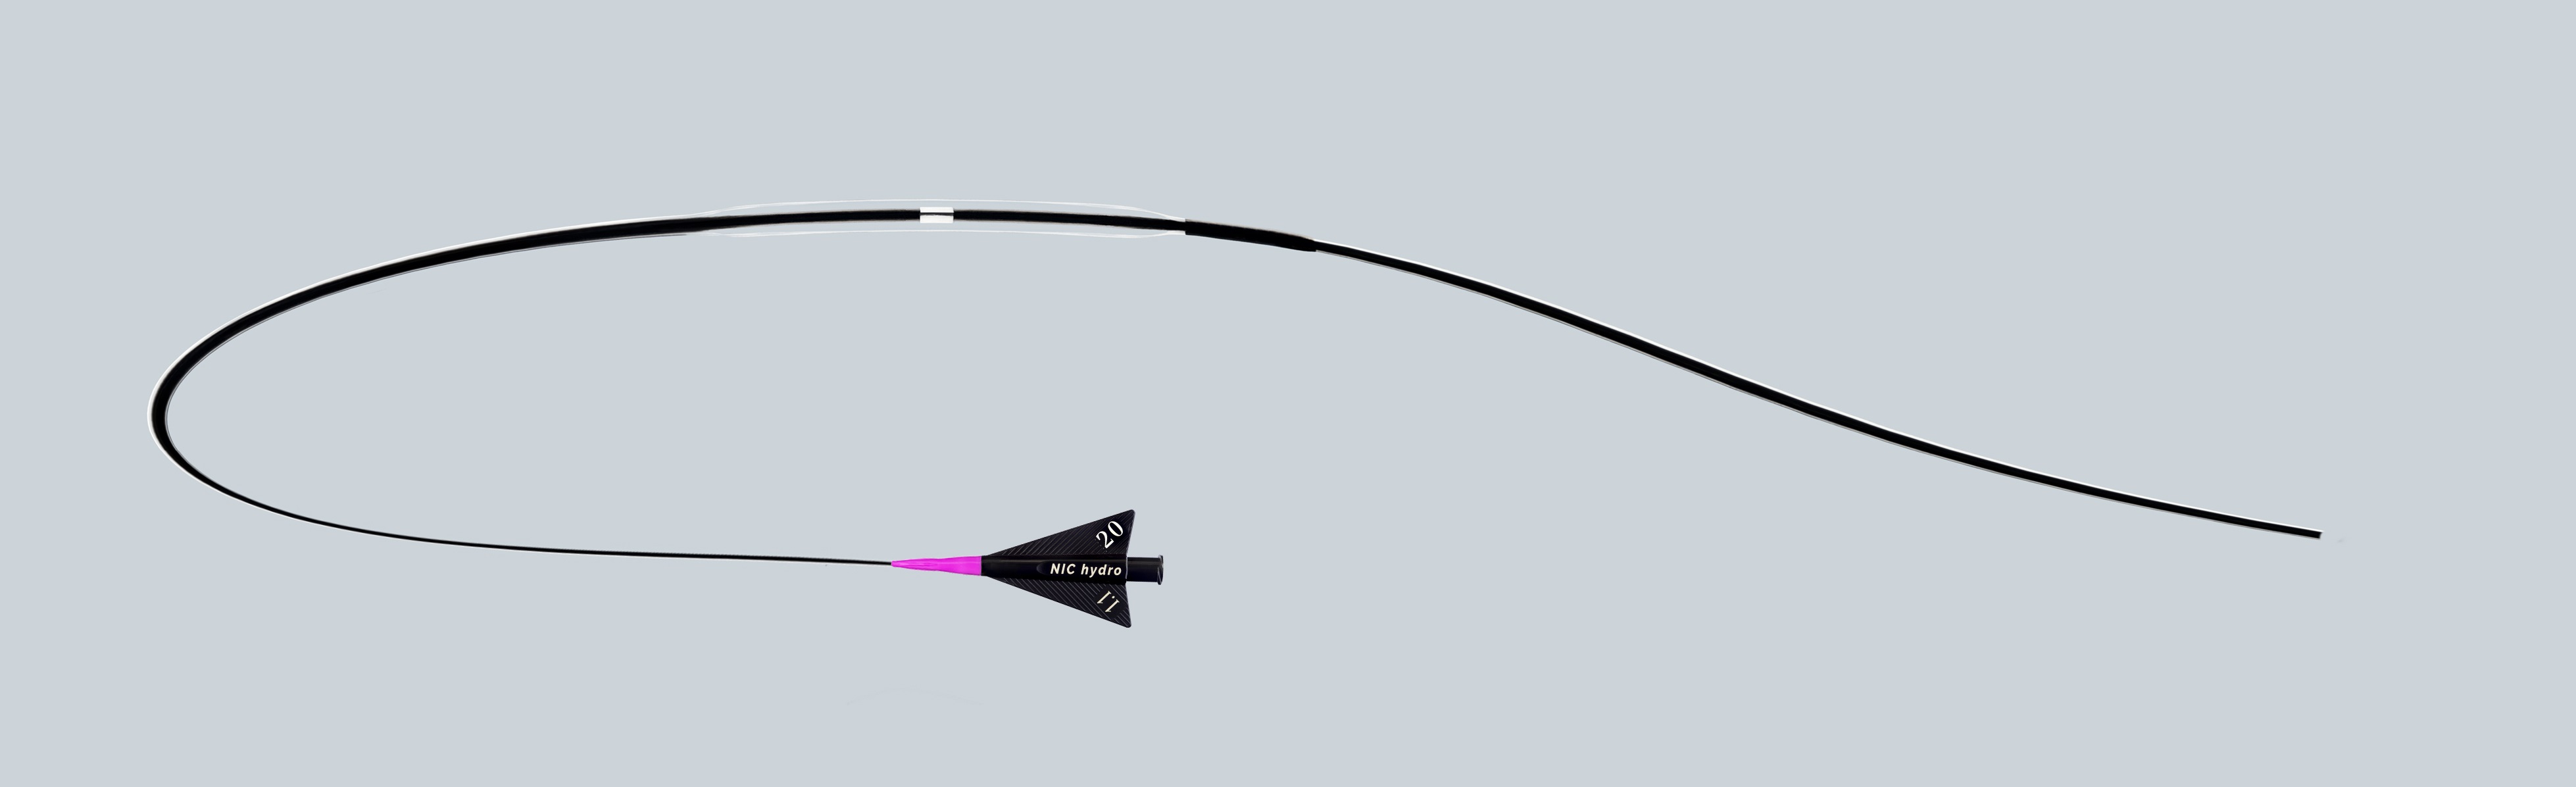

SIS Medical, founded in 2007 is a Swiss based medical company dedicated to the development, production and distribution of innovative very high performance PTCA balloon catheters which is specifically designed to extend treatment options. They manufacture high and super high pressure PTCA balloons for targeting unmet clinical needs with regular PTCA balloons such as undilatable lesions and in-stent restenosis.